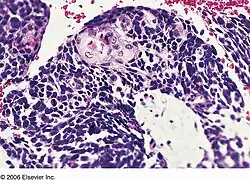

Combined small cell lung carcinoma containing a component of squamous cell carcinoma

Combined small cell lung carcinoma (or c-SCLC) is a form of multiphasic lung cancer that is diagnosed by a pathologist when a malignant tumor, arising from transformed cells originating in lung tissue, contains a component of small cell lung carcinoma (SCLC) mixed with one or more components of any histological variant of non-small cell lung carcinoma (NSCLC) in any relative proportion.[1][2][3]